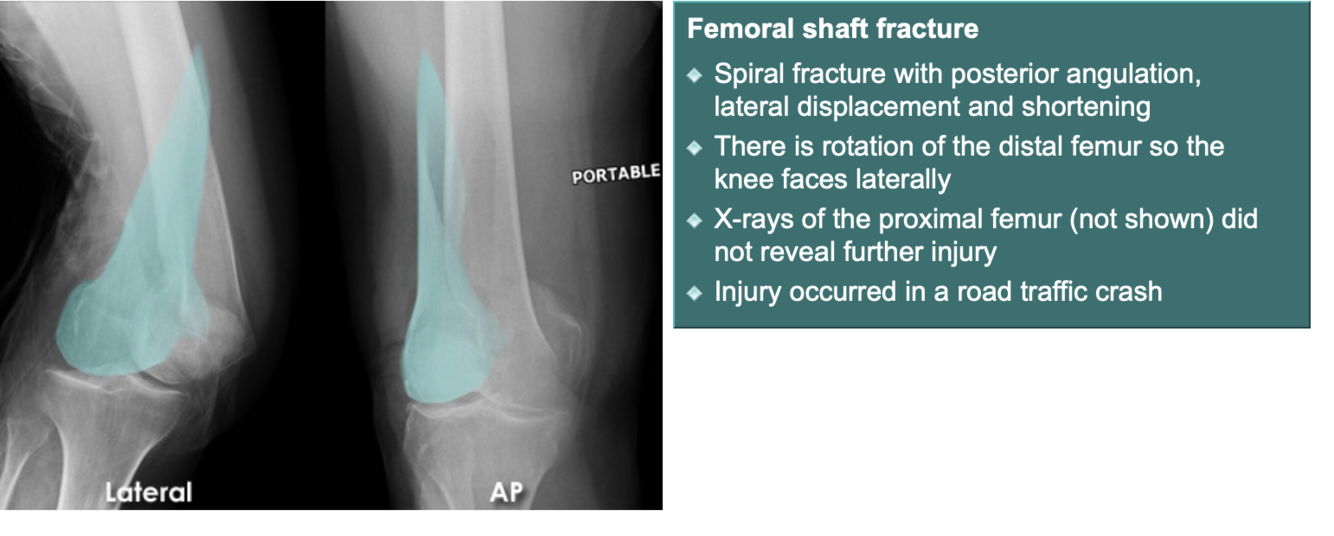

Describe the fracture seen in this X-ray [1]

A

Lateral tibial plateau fracture

* The fracture fragment is displaced and depressed from its normal position (dotted line)